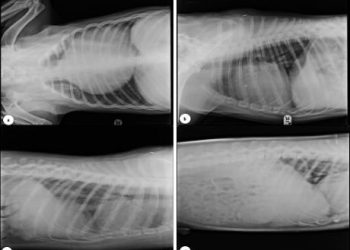

Evrim EGEDEN1, Sinem Yaren AKGÜL2, Sümeyye TOYGA2, Büşra İNAL GÜNAY3, Funda YILDIRIM4 1Ada Veteriner Polikliniği, 34330, Beşiktaş, İstanbul, Türkiye...

Evrim EGEDEN 1 , Vakkas Can SERT 2 , Sümeyye TOYGA 3 , Sinem Yaren AKGÜL 3 , Gülay YÜZBAŞIOĞLU...